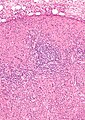

Kikuchi disease. H&E stain. | |

| LM | histiocytes, necrosis (paracortical areas) without neutrophils, bland lymphocytes, plasmacytoid dendritic cells |

Features (the three main features - just as the name suggests):[5]

- Histiocytes.

- May be crescentic.

- Necrosis (due to apoptosis) - paracortical areas.[2]

- Necrosis without neutrophils - key feature.

- Lymphocytes (CD8 +ve).

- Plasmacytoid dendritic cells.